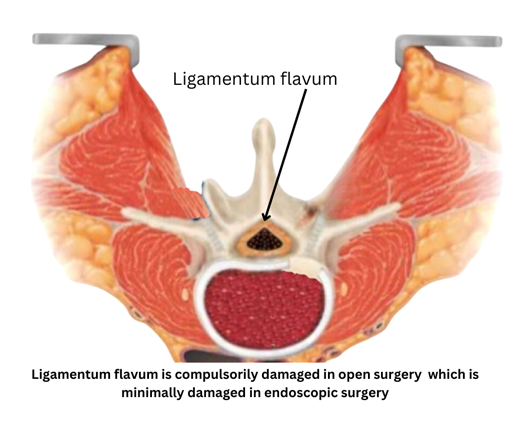

Ligamentum flavum:

Ligamentum flavum acts a very important barrier between the nervous structures and muscles. Its damage causes adhesions between these two structures and neurogenic pain secondry to these adhesions. All open surgeries damage this ligament but with endoscopy we can bypass this ligament or limit its damage to the minimum.